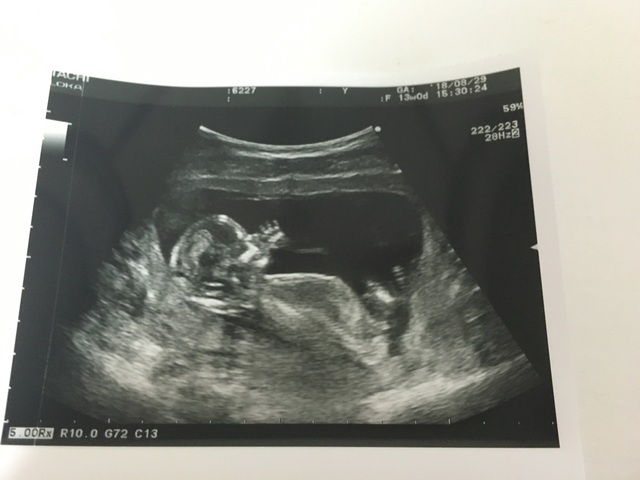

13週0日(13w0d・男の子)|ひるじゅん さん(35歳)

エコー写真撮影時のエピソード:

呑気に指しゃぶりしているところがかわいい。

2人目の妊娠なので、家族みんな性別が早く知りたかったけど、こんなに良く見えているのに、この時はまだお股をはっきりは見せてくれなかった。

食事面を含め、2人目妊娠は神経質にならず過ごした。気にしなすぎくらい…。